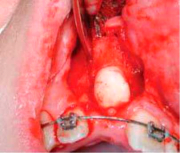

| 09:13, 19 ביוני 2013 | אנקילוטית7.png (קובץ) |  |

135 קילו־בייטים | Motyk | 1 | |